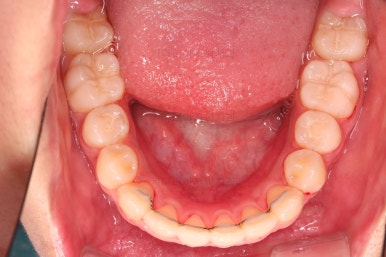

부산치아교정치과 키다리아저씨치과에서 마무리한 입안의 모습입니다.

가지런하게 잘 정렬이 되었고요.

윗니만 발치한 편악발치교정이지만 틈새 없이 공간이 닫혔으며 교합도 잘 맞습니다.

위아랫니가 가지런하게 보기 좋게 배열이 되었고요.

아랫니까지 윗니를 넣음으로써 튀어나와 보이던 앞니의 느낌이 좋아졌습니다.

물론 작은 아래턱에 맞춰 윗니를 뒤로 집어넣어야 해서 자칫 지나치게 들어간 입이 될까 염려되는 조심스러운 케이스였지만, 편악발치를 통해 최소한으로 입을 넣으면서 굉장히 조화롭게 잘 마무리 했습니다.